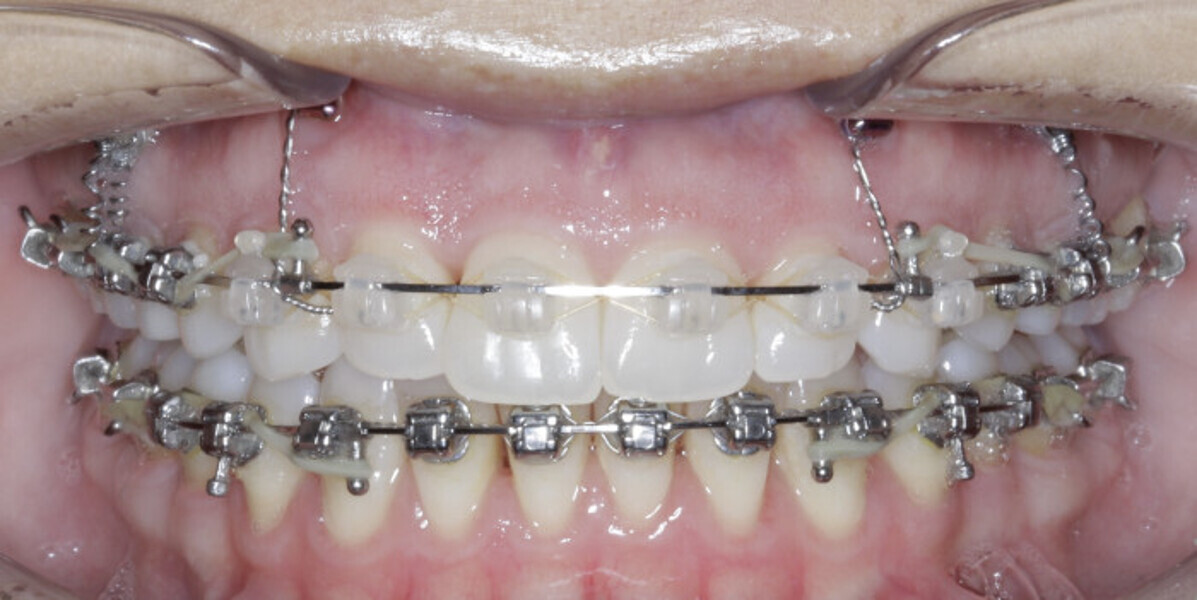

New Age orthodontics and orthopaedics with temporary anchorage devices